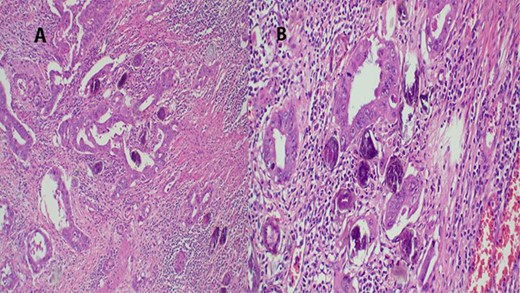

An abdominal ultrasound showed a mass in the posterior wall of the urinary bladder measuring 6 cm × 7 cm with areas of necrosis. There was left moderate ureter hydronephrosis. The right kidney and the rest visceral organs were normal. Chest X-ray revealed multiple macronodules all over the lung fields. Heart size, costophrenic and cardiophrenic angles were all normal (Fig. 6).

Urethrocystoscopy found to have extensive sand patch lesion in the urinary bladder with solitary solid tumor on the right side of the bladder wall extending from 3 to 5 o’clock. A transurethral resection of bladder tumor biopsy (TURBx) was done, and histological findings confirmed adenocarcinoma of the bladder with numerous calcified submucosal Schistosoma eggs (Fig. 7).

(A) Histopathology of urinary bladder with invasive adenocarcinoma, not otherwise specified (NOS), H&E ×10 magnification. (B) Schistosoma ova near or within the tumor, ×4 magnification.

The final diagnosis of metastatic adenocarcinoma of the urinary bladder was made and the patient was referred for palliative radiation therapy.